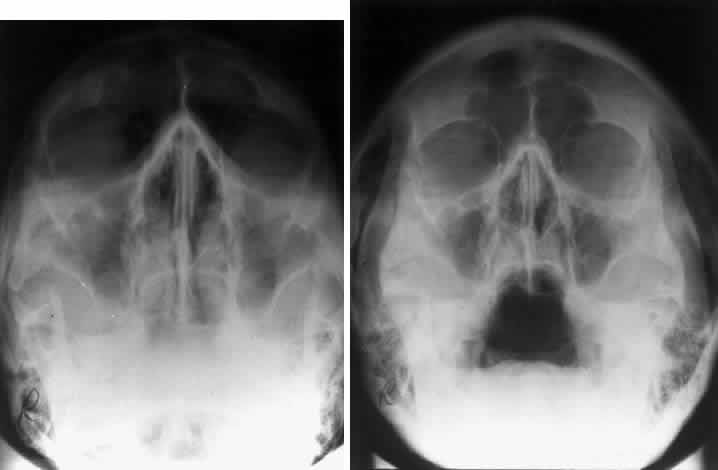

The localization of foreign bodies with plain films is a recurring challenge. Echography and CT have diminished the need for plain film techniques for localization of foreign bodies, but the latter can be used when other imaging modalities are unavailable. Frontal and lateral projections are standard views in these studies (Fig. 18). Localization of a foreign body within the globe is possible with bone-free examination using dental film or by ocular rotation. This latter study localizes the foreign body to either the anterior or posterior segment of the eye. If the foreign body is anterior, the object will rotate in the same direction as the eye. The object will move in an opposite direction to eye movement if its location is in the posterior segment of the eye33 (Fig. 19). Pfeiffer34 and Worst35 used contact lenses as reference devices in localizing foreign bodies. These techniques are less commonly used.

Fig. 19. Foreign body localization using the ocular rotation technique. The patient is directed to look up, as in A, which shows the foreign body moving in the direction of upgaze. B. Foreign body is seen in an inferior location after the patient looked down. This foreign body was located in the anterior segment of the eye.